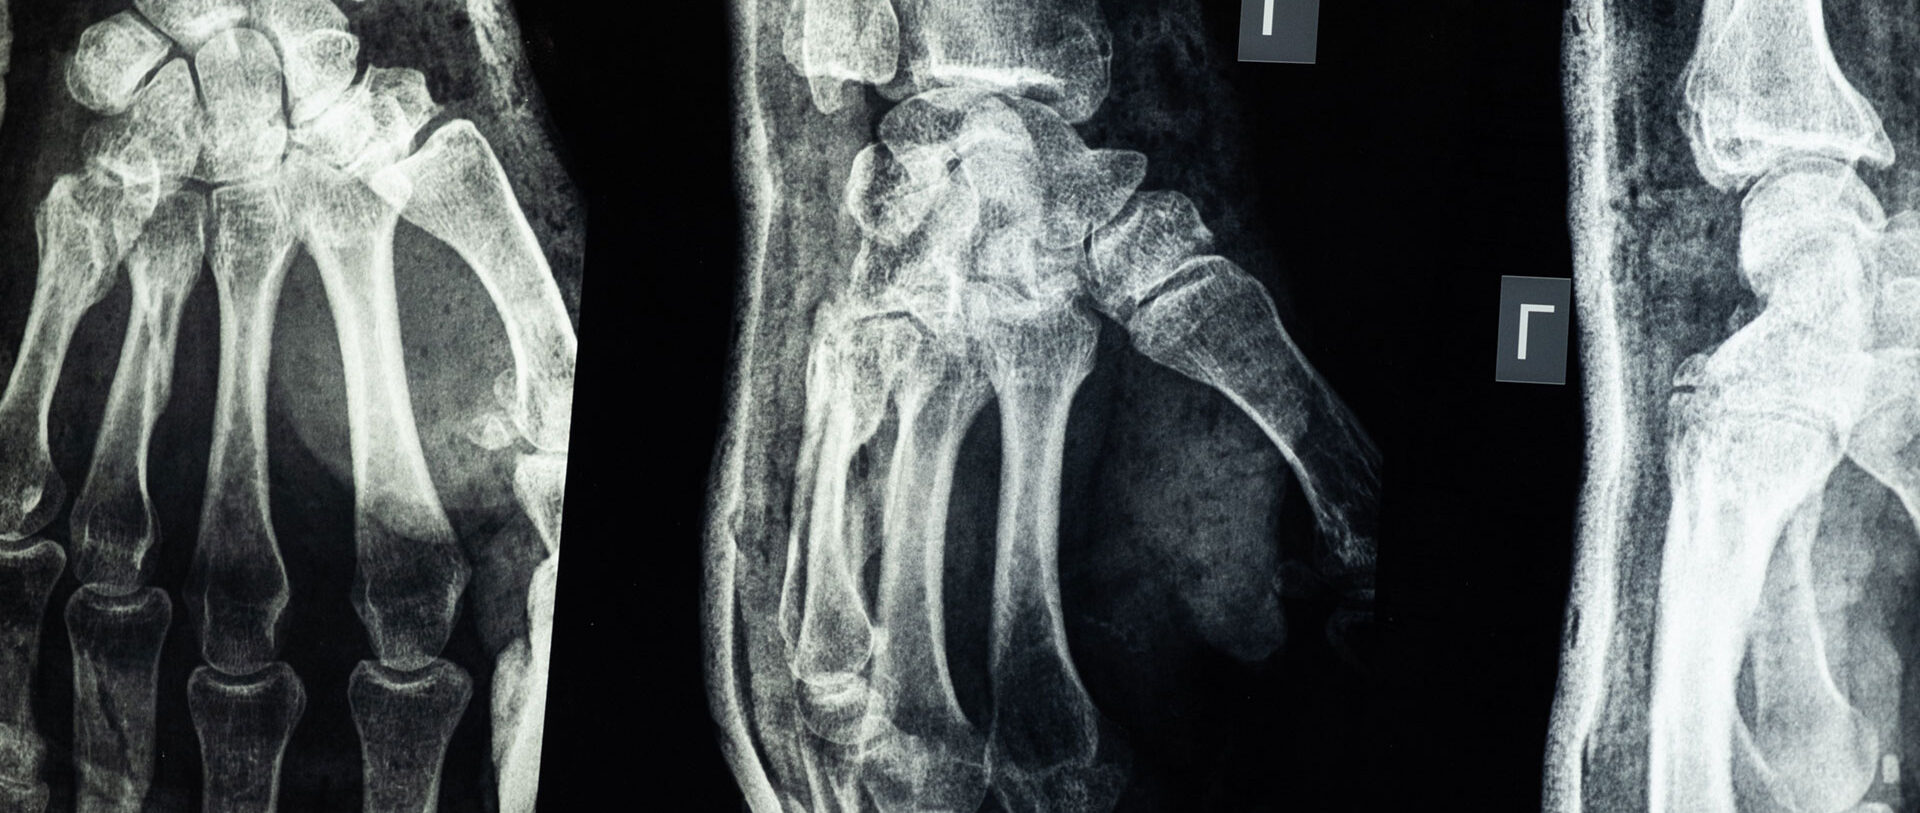

Unitat de la mà, canell i colze

La cirurgia de la mà i del canell presenta una alta exigència tècnica i requereix una habilitat i entrenament específics. Aquesta unitat presenta la següent activitat:

- Cirurgia de malalties degeneratives.

- Cirurgia de la mà i el canell reumàtic.

- Cirurgia tumoral.

- Cirurgia tendinosa.

- Terapia biològica articular i miotendinosa.

- Cirurgia dels trastorns nerviosos.

- Cirurgia plàstica.

- Cirurgia de la mà pediàtrica.

- Cirurgia traumàtica diferida i de les seqüeles traumàtiques.

- Artroscòpia de canell i colze.

- Microcirurgia.

- Cirurgia protètica de mà canell i colze.